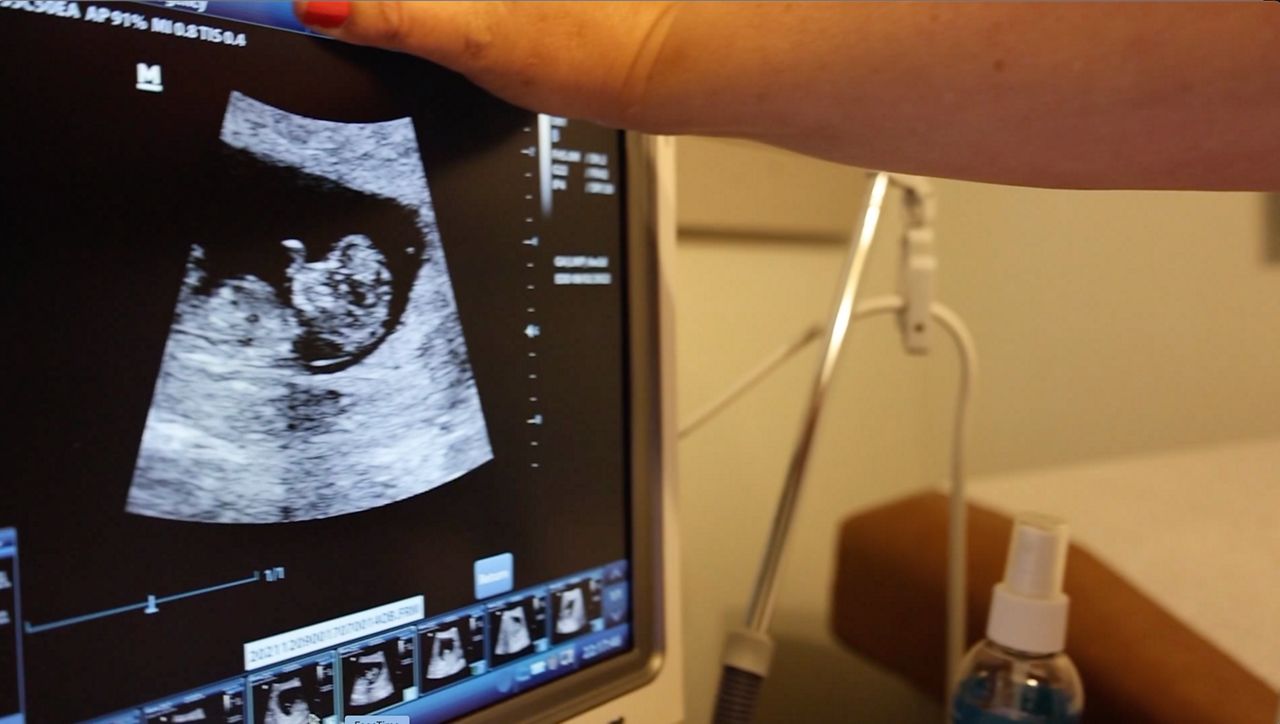

Antidepressants are a widely accepted treatment for pregnant women experiencing mental health disorders. But last week, several members of an FDA panel expressed their concern surrounding the use of selective serotonin reuptake inhibitors or SSRI’s — like Lexapro or Zoloft — during pregnancy.

Urato, the chief of maternal fetal medicine at MetroWest Medical Center in Massachusetts, was one of several panelists who expressed concern over how SSRIs may affect development, both in utero and after birth.